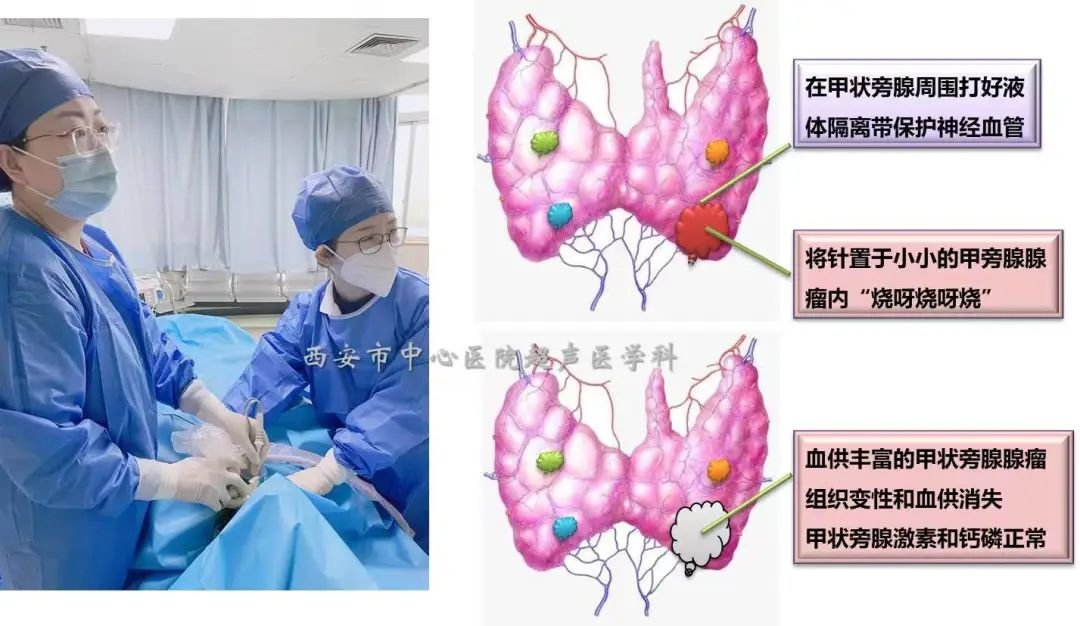

65岁的张女士平时感劳累及腰腿疼,轻度骨质疏松等,2个月前超声检查时发现左侧颈部低回声包块,位于甲状腺左叶背面下极,血供较丰富,形态不规则,活检证实为增生的甲状旁腺,一抽血惊讶的发现甲状旁腺激素已升高至139.1 <正常15-65> pg/ml,血钙已升高至2.81mmol/L。妥妥的甲状旁腺功能亢进!

局麻条件下,在超声实时监测下通过精细的液体注射隔离,将包块周围的神经、血管、甲状腺下极等完美的隔离保护起来,用细细的一根针进入腺瘤内,强回声的热气很快覆盖了腺瘤,一气呵成,仅仅不到10分钟便完成了整个手术,超声造影下血供丰富的高增强腺瘤结节完美的演变为无增强的“黑洞”,手术过程非常顺利,患者仅感到一点点灼热感,皮肤局部仅一个针眼,患者消融完便自行走回了病房。一天后,患者化验室检查数值回归正常水平,无其他不良反应。

术前高增强腺瘤,术后为充盈缺损